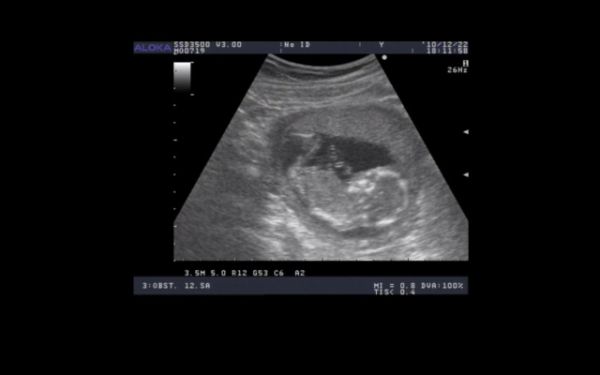

jah, és ahhoz, hogy ikrek még külön!